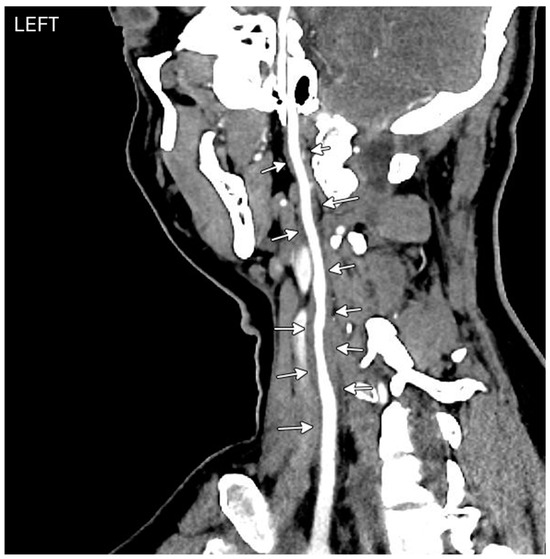

Central Retinal Artery Occlusion Associated with Takayasu Arteritis

Mumtaz, S.; Wilson, C.; Vibhute, P.; Eggenberger, E.R.; Berianu, F.; Abril, A. Central Retinal Artery Occlusion Associated with Takayasu Arteritis. Diagnostics 2024, 14, 1329. https://doi.org/10.3390/diagnostics14131329